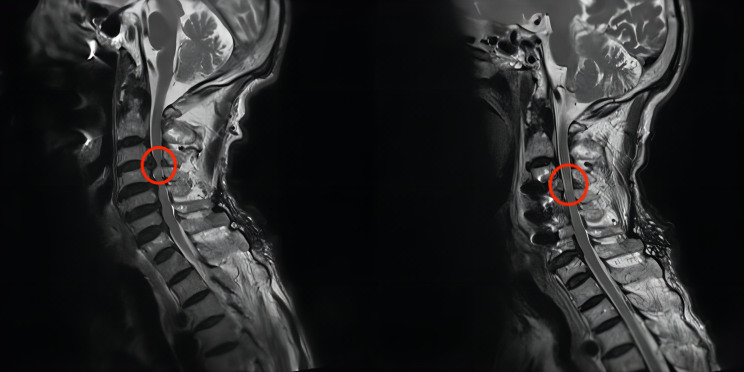

74歲的孫爺爺,因全身乏力,癱倒在床一月有余,家人帶其四處求醫始終未見好轉,在幾乎要陷入絕望時,決定前往我院神經外科進行咨詢。神經外科脊柱脊髓組鄧雷副主任醫師仔細查看孫爺爺的核磁共振結果影像,顯示脊髓受壓嚴重,僅剩一條狹窄的縫隙。針對孫爺爺復雜的病情,以及高齡的情況,經與患者及家屬積極溝通,鄧雷副主任醫師決定為其實施顯微鏡下三節段ACDF。